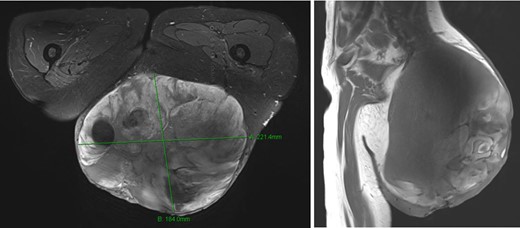

A woman 36 years of age presented with a painless, slowly growing mass of the left buttock (Fig. 1). Magnetic resonance showed an inhomogeneous tumor of 10 × 8.5 × 6 cm3 in size suspicious for myxoid sarcoma (Fig. 2). Biopsy was recommended. However, the patient refused and was lost for follow-up. Three an a half years later, the anemic patient was referred again, now with a giant 22 × 19 × 24 cm3 measuring, foul, ulcerating and bleeding tumor (Fig. 3), partly infiltrating the gluteus maximus muscle (Fig 4). Myxoid sarcoma was confirmed by three deep punch biopsies in local anesthesia followed by swift surgical resection.

Magnetic resonance imaging showed a very large tumor of the left gluteal region, further infiltrating the left gluteus muscle and now with infiltration of the skin.

The patient was put in prone position under general anesthesia and the operating site desinfected with Povidone Iodine solution. The operation field was additionally covered with an Iodine impregnated incision drape to further minimize bacterial contamination. The skin was incised circumferentially, minimally 1 cm away from the palpable tumor mass, until reaching the fascia of the gluteus maximus muscle. The tumor was then resected circumferentially including parts of the gluteus maximus muscle and its fascia leaving the sciatic nerve and the external anal sphincter untouched. Wound closure was achieved after epifascial mobilization, followed by uneventful wound healing and an acceptable aesthetic result (Fig. 5). Pathohistological workup confirmed wide resection (R0) of an intermediate grade myxoid liposarcoma Grad 2 according to the French Federation of Comprehensive Cancer Centers (FFCCC), weighing 5.6 kg and measuring 26 × 24 × 15 cm3. After interdisciplinary discussion at the in-house sarcoma board, no radiation therapy was recommended.